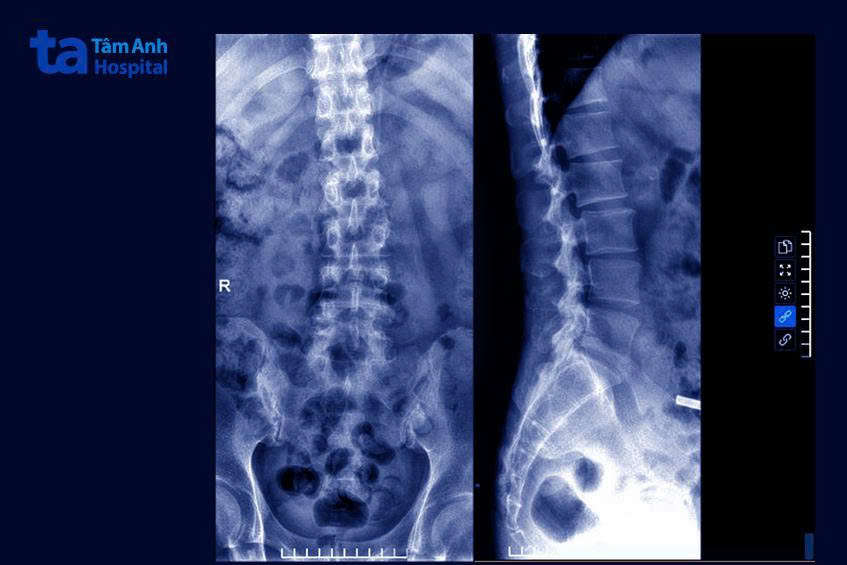

Từ phim chụp X-quang thấy khe khớp cùng chậu mờ, đặc xương hai bên, chụp cộng hưởng từ MRI thấy phù tủy xương bờ khớp cùng chậu, PGS Hoa chẩn đoán anh Quang mắc viêm khớp cột sống chồng lấp bệnh gout, khiến việc điều trị gout đơn thuần trước nay không hiệu quả.